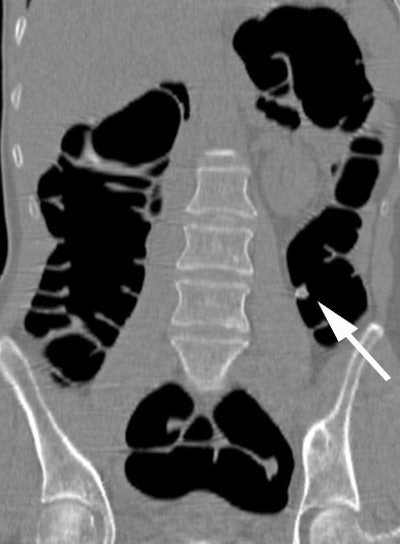

| Sagittal VC image confirms the presence of the polyp (arrow) within the descending colon. Image courtesy of Dr. Riccardo Iannaccone. |

Results from the first 130 patients showed that the positive predictive value was 79.3% and the negative predictive value (NPV) was 96%, Iannaccone said in his RSNA presentation. "This is a very important result, because NPV represents the ability of CTC to identify patients without colorectal polyps," he said.